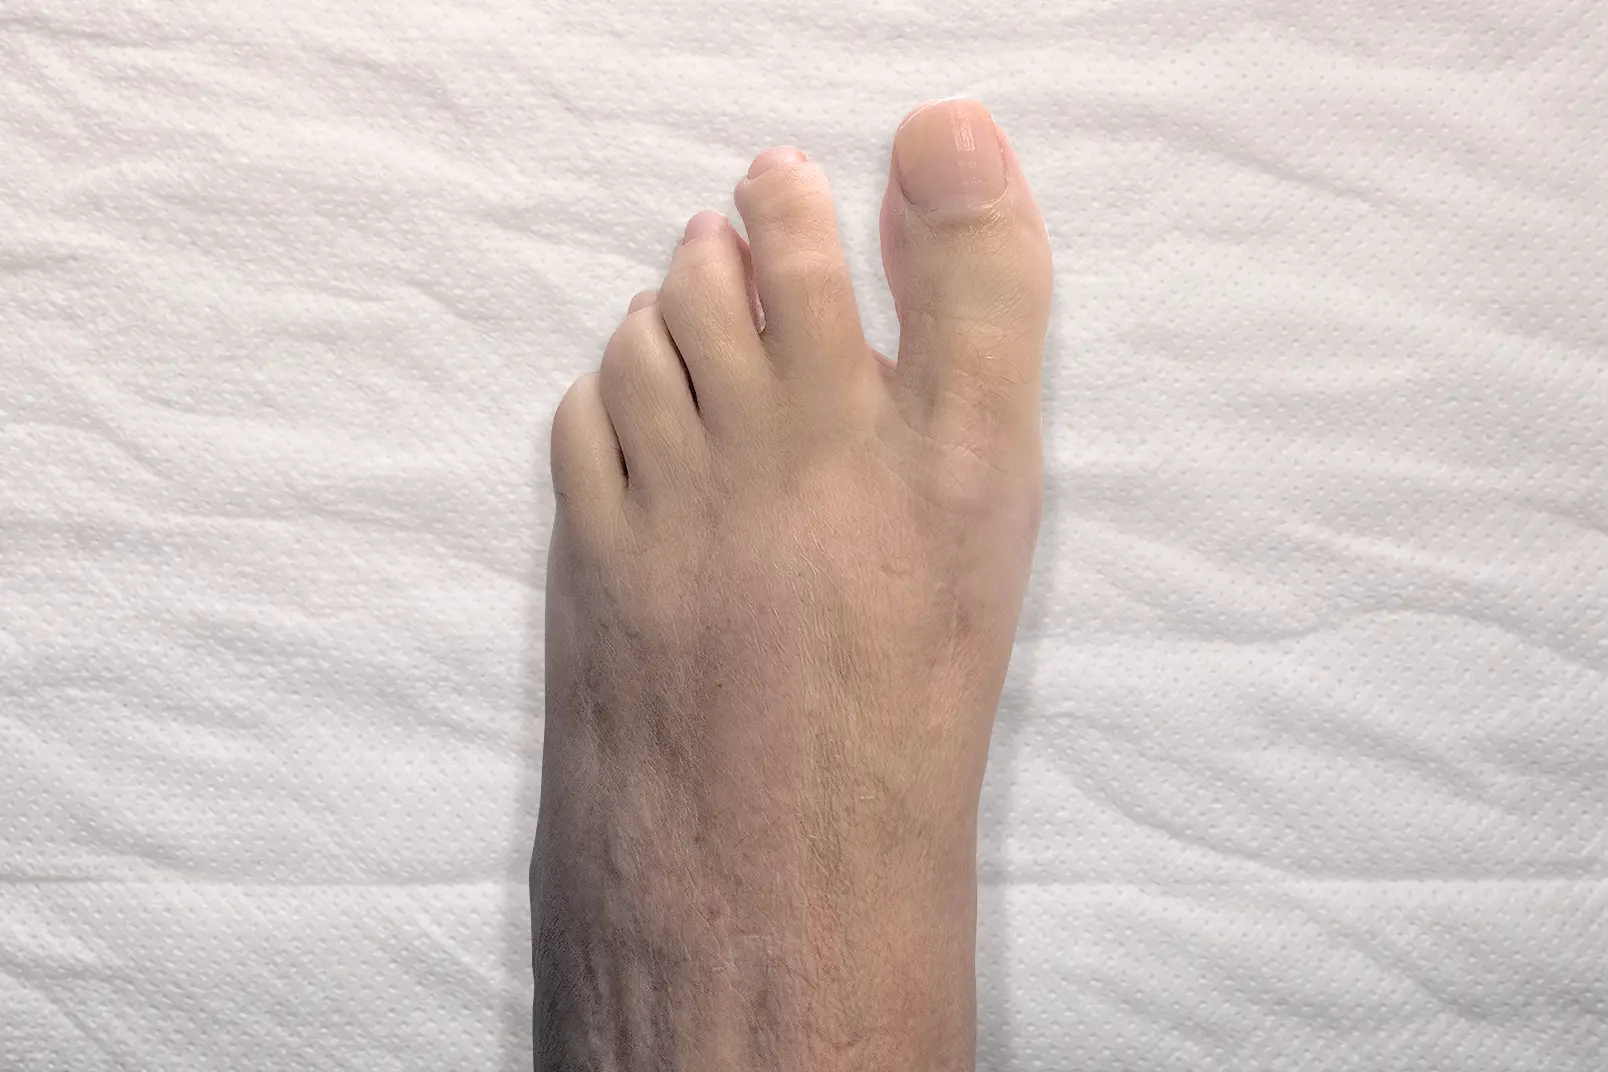

Cirugía de

deformidades

del antepié

El antepié concentra muchas de las patologías quirúrgicas más habituales. Son problemas que suelen avanzar con el tiempo y que, cuando generan dolor o deformidad progresiva, pueden limitar de forma importante la vida diaria. Nuestra especialización quirúrgica, buscando la mínima invasión y la rápida recuperación, incluye, entre otras, la cirugía de:

- Juanetes (hallux valgus).

- Metatarsalgia.

- Neuroma de Morton (radiofrecuencia o cirugía).

- Deformidades de los dedos (dedo en martillo, dedo en garra, dedo en mazo, dedo crossover).

- Reconstrucción del antepié.

- Hallux limitus y hallux rigidus (artrosis del dedo gordo del pie).

En muchos de estos casos el paciente ha probado previamente plantillas, cambios de calzado o tratamientos conservadores. Cuando la deformidad progresa o el dolor persiste, la cirugía del pie permite corregir la causa del problema y mejorar la función.